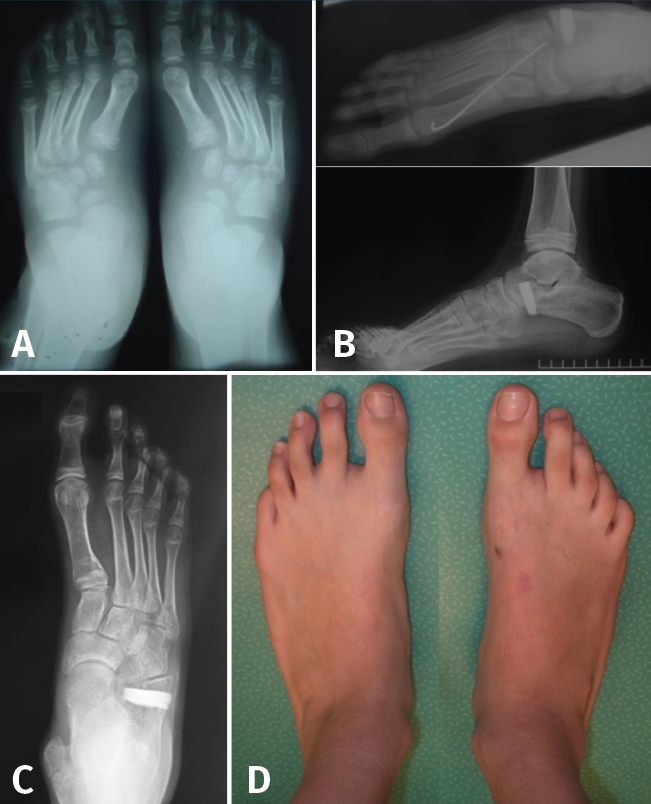

Radiografía dorsoplantar en carga (Figura 5)

Figura 5. Radiografía dorsoplantar en carga. Ángulo Kite (azul). Ángulo C5M (verde). Ángulo del eje del astrágalo y el eje del primer metatarsiano (rojo). Ángulo de descobertura talonavicular (negro).

- Ángulo astrágalo-calcáneo (AC) o de Kite (normal entre 20 y 30°): su aumento es el reflejo de la divergencia AC aumentada en el PPV de componente subtalar.

- Ángulo entre el borde lateral del calcáneo y el eje longitudinal del quinto metatarsiano (C5M): su alteración se correlaciona con la abducción del antepié, siendo su valor normal 0°.

- Ángulo entre el eje del astrágalo y el eje del primer metatarsiano (valores normales de 0 a 5°). Este ángulo es útil para determinar el componente de metatarso aducto. Asociado a una divergencia AC aumentada, orienta a un pie en serpentina o en Z.

- Valoramos la cobertura TN con el ángulo de descobertura TN (valores normales de 10°) o con el porcentaje de descobertura de la cabeza del astrágalo (si > 40%, indica deformidad en abducción severa)(7).

Radiografía lateral del pie en carga (Figura 6)

Figura 6. Radiografía lateral del pie en carga. A: pie normal; B: pie plano. Ángulo de Meary (rojo). Ángulo de Costa-Bartani (azul). Calcaneal pitch angle (negro).

- Ángulo de Costa-Bartani: mide el arco longitudinal medial y está definido por 2 líneas que unen respectivamente los puntos más bajos del calcáneo, el astrágalo y la cabeza del primer metatarsiano, siendo normal entre 125 y 135°. Aumentado en PPV, es una medida del aplanamiento del arco interno.

- Ángulo de Meary (ángulo lateral del astrágalo-primer metatarsiano): su valor normal es entre 0 y 10°. Este ángulo también es una medida del aplanamiento del arco interno y está alterado en los diferentes patrones de pie plano (media de 35°).

- Calcaneal pitch angle (ángulo de inclinación del calcáneo): es normal entre 20 y 30°. Está disminuido en todos los patrones de pie plano, excepto en el patrón de pie plano cavo, que está aumentado.